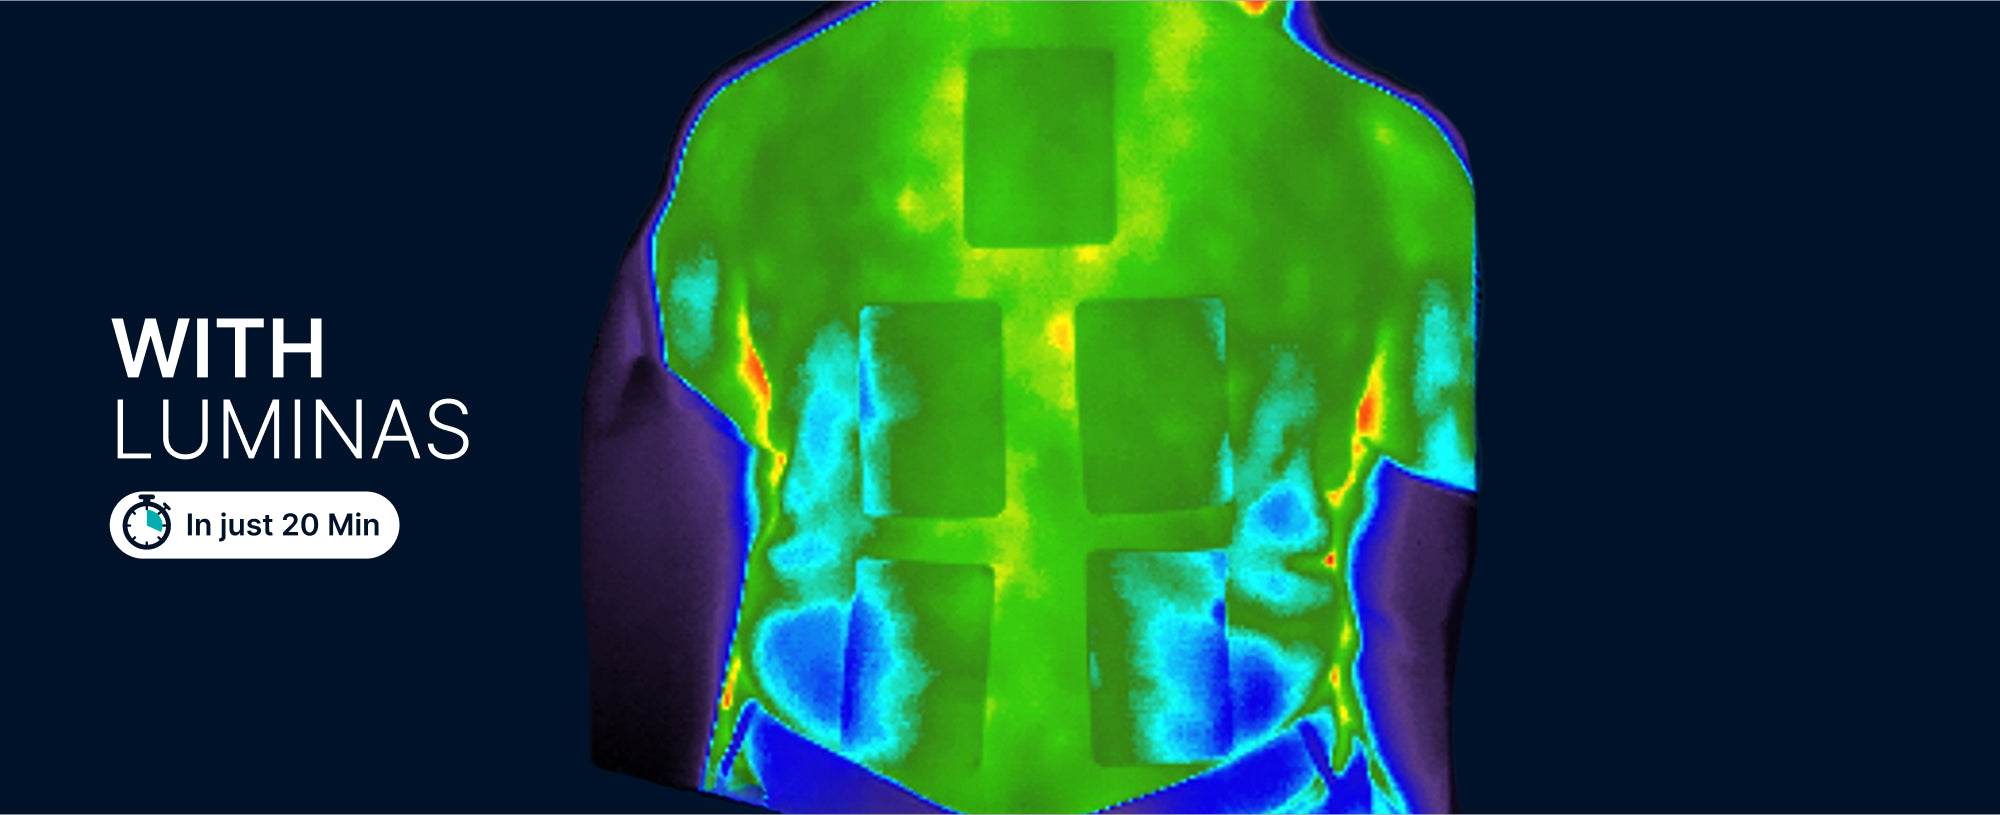

Reduced Inflammation For 94% of Patients!

Using digital infrared thermography, skin temperature (inflammation) was notably reduced.